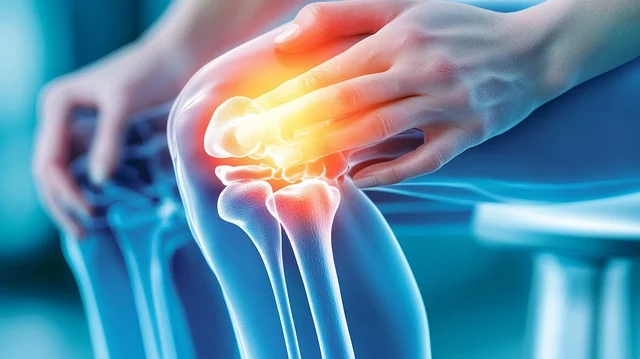

퇴행성 관절염은 노화나 반복적인 관절 사용으로 인해 연골이 닳아 발생합니다. 주로 무릎, 엉덩이, 손가락 관절에서 자주 나타납니다.

류마티스 관절염은 자가면역 질환으로, 신체의 면역체계가 자신의 관절을 공격하면서 염증이 생기는 병입니다. 주로 여성에게 많이 발생하며, 조기에 발견하지 않으면 관절 손상이 진행될 수 있습니다.

A1. 관절염 초기 증상을 방치할 경우, 염증과 통증이 점점 심해져 관절 손상이 가속화될 수 있습니다. 결국 관절 기능이 저하되고 심할 경우 수술이 필요할 수 있으므로 초기 증상을 발견하면 빠르게 관리하는 것이 중요합니다.

관절염은 초기 증상을 빠르게 알아차리고 관리하는 것이 중요합니다. 초기에는 간헐적인 통증과 경직으로 시작되지만, 이를 방치하면 점차 관절 손상이 심해질 수 있습니다. 퇴행성 관절염과 류마티스 관절염의 초기 증상은 다소 차이가 있으므로, 자신의 상태를 정확히 파악하고 조기에 대처해야 합니다.